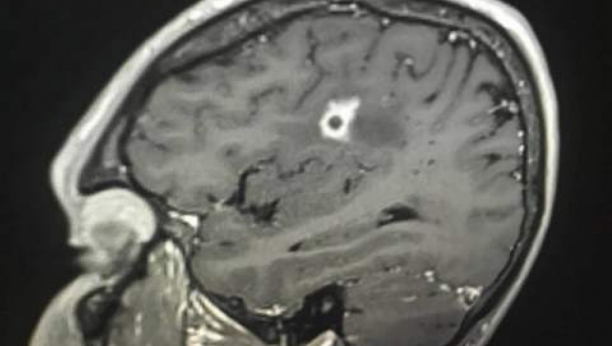

Tajson Botenus je kontaktirao svog doktora u vezi sa svojim problemima, i on je predložio MR, koji je pokazao čudan krug u sredini njegovog mozga. Bio je to početak teškog putovanja da se identifikuje tajanstveni krug.

Nakon dve neuspele biopsije mozga, u pokušaju, lekari u Opštoj bolnici u Masačusetsu otkrili su uzrok Tajsonovih problema. Tokom testiranja na drugu vrstu raka mozga, pronašli su crnu gljivicu u njegovom mozgu, za koju su laboratorijski testovi potvrdili da je Cladophialophora bantiana, ili crna buđ (plesan).